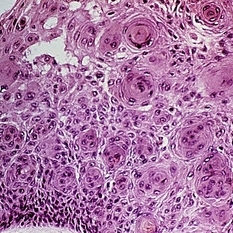

Slide 5-34 Slide 5-34Feb 25 2019 by Lancaster Course in Ophthalmology Large nuclei of an ulceronodular basal cell carcinoma can be compared with the adjacent normal epithelial cell nuclei. Note the peripheral palisading of the nuclei around the edge of the tumor lobules. Condition/keywords: basal cell carcinoma of eyelid, epithelial, nuclei